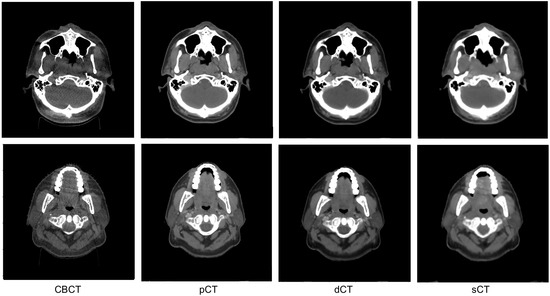

3.1. Image Quality Evaluation with Quantitative Metrics

3.2. Image Quality Evaluation in Preserving Anatomy